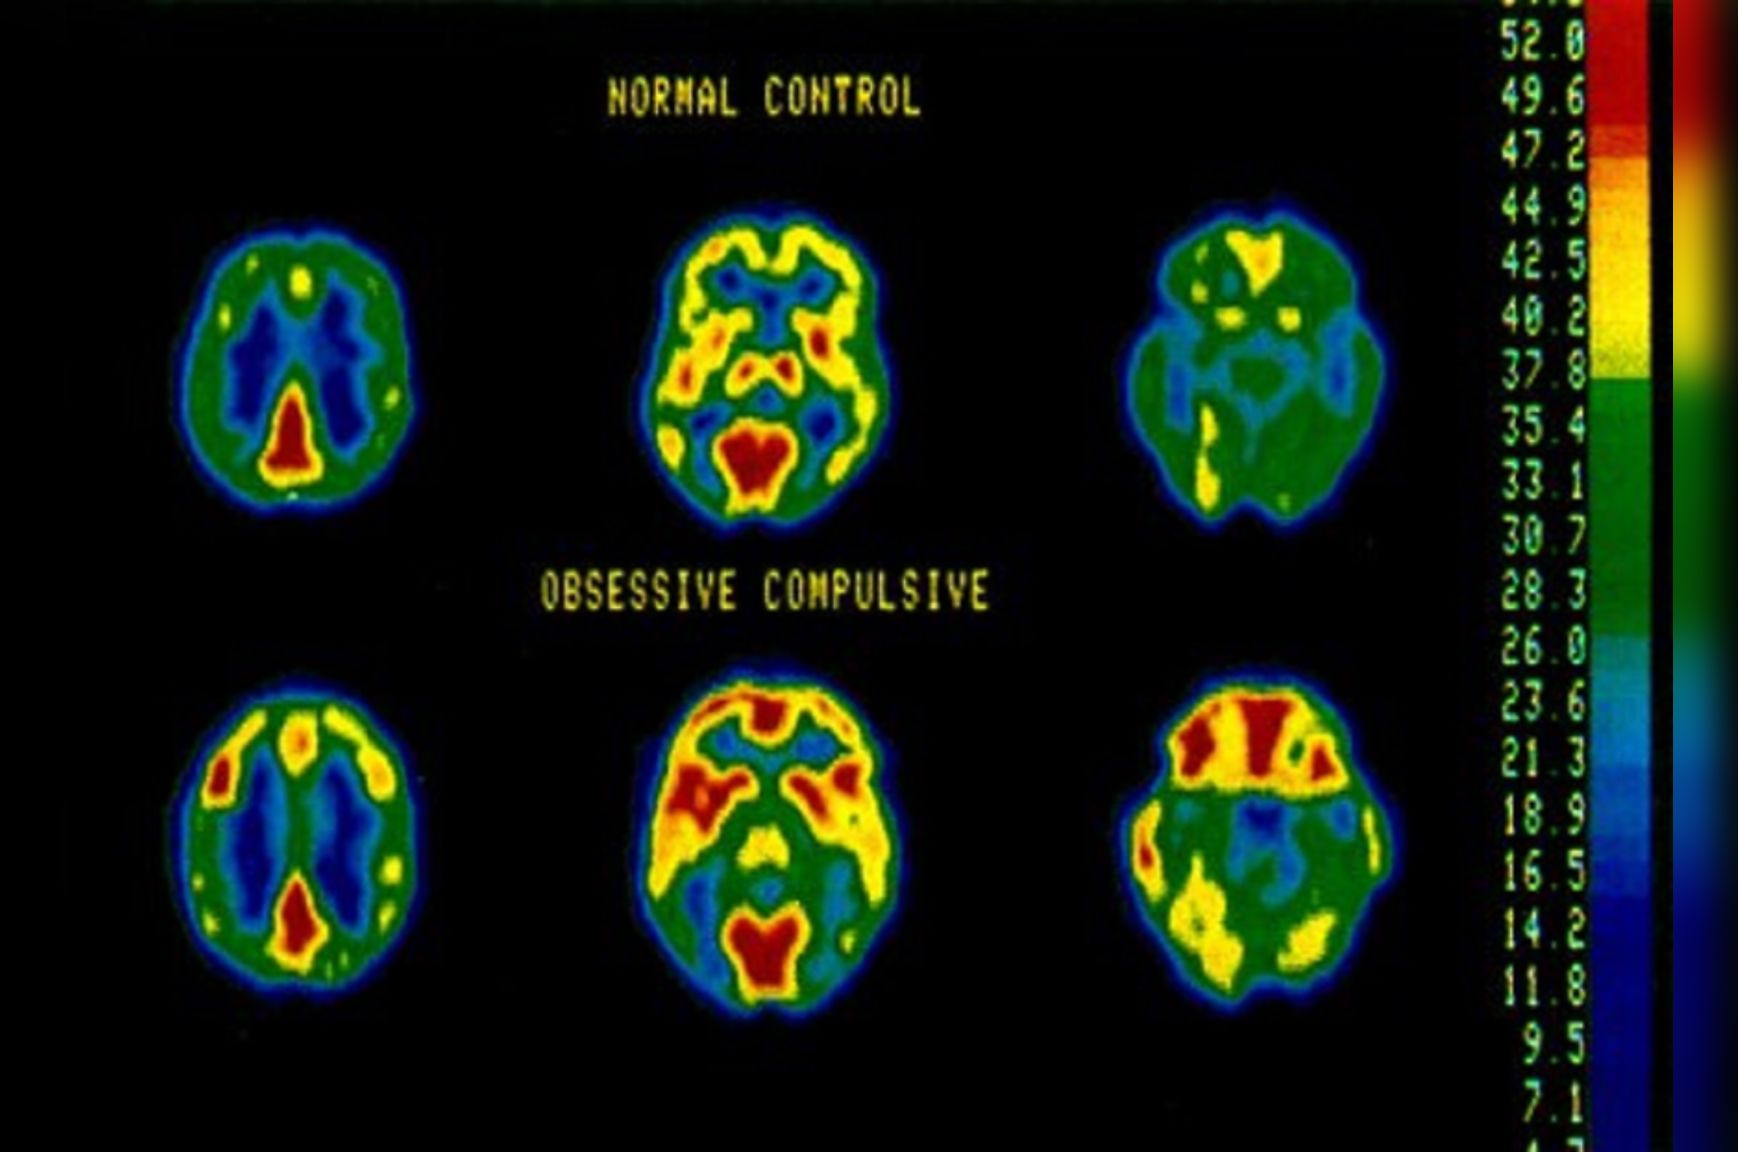

OCD is not a character flaw, a choice, or a result of weak willpower. It’s a legitimate neurobiological condition that affects brain circuits involved in decision-making, habit formation, and anxiety regulation. People with OCD are dealing with a medical condition that responds well to proper treatment.